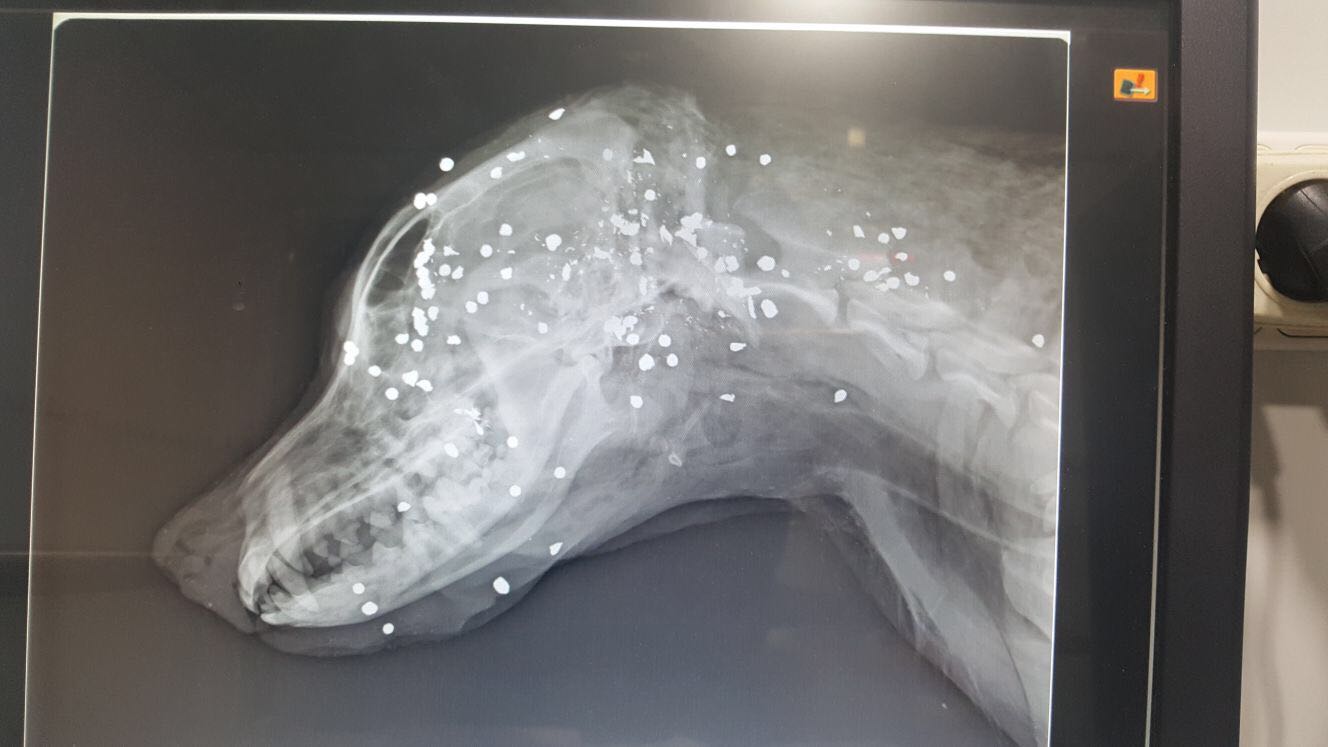

"Ha quedado claro, una vez hecha la necropsia, que el perro murió por un disparo en la cabeza con escopeta de caza. El esfínter aparece dilatado porque llevaba ocho o nueve días muerto y eso es algo frecuente, pero no ha habido lesión anal, ni señales de quemadura tras examinar el cuerpo. Hemos entrado en contacto con las protectoras de animales, hemos congelado el cuerpo, nos vamos a personar para que si el Juzgado pide analizar el cuerpo, está ahí; pero hay que parar la imagen tan lamentable que se está transmitiendo de Benalup por este caso aislado", han confirmado fuentes municipales a lavozdelsur.es.